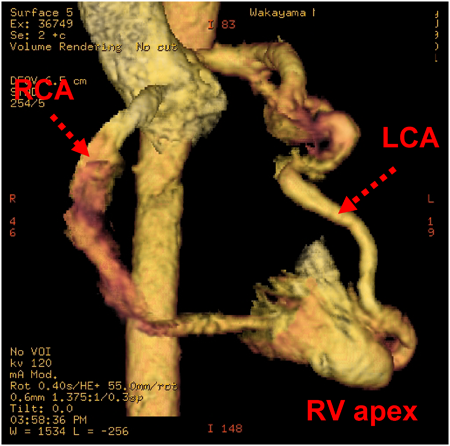

5)冠動脈CT

両側冠動脈の拡大,蛇行を認める.両側右室心尖部への流入を認める(Fig. 1).

Pediatric Cardiology and Cardiac Surgery 32(3): 232-236 (2016)

Fig. 1 Preoperative three-dimensional reconstruction computed tomography showing dilated RCA and LCA drain into the RV apex

RCA, right coronary artery; LCA, left coronary artery; RV, right ventricle.